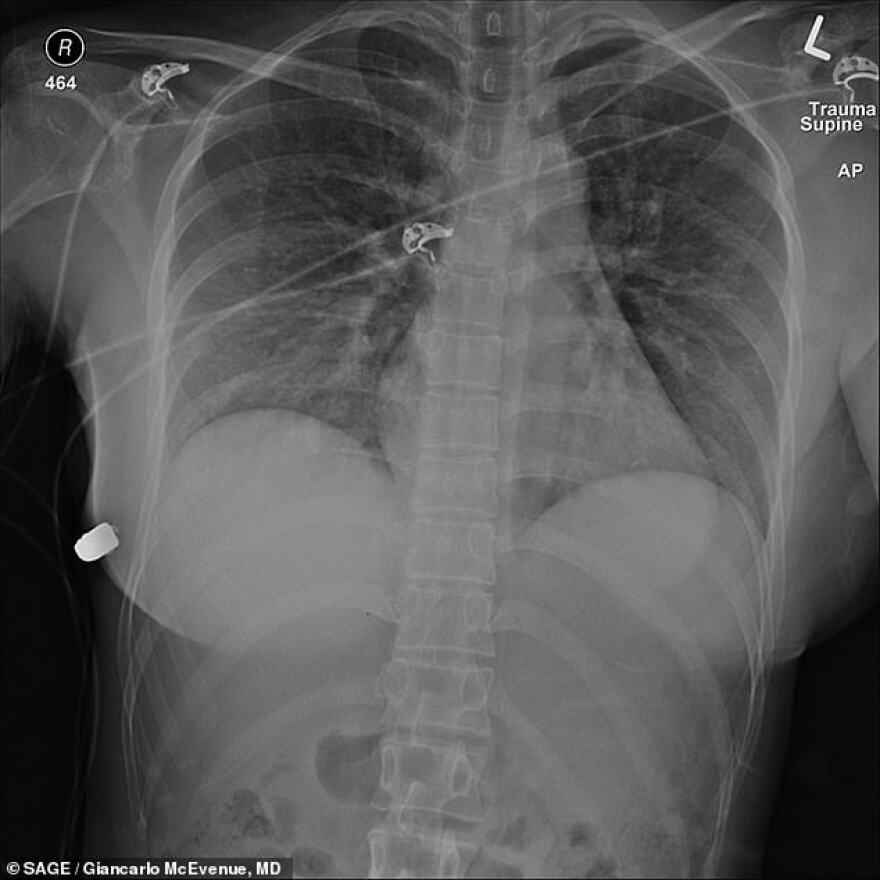

Οι ακτινογραφίες της 30χρονης έδειξαν την σφαίρα καρφωμένη πάνω στο εμφύτευμα ενώ στην έκθεση που δημοσιεύτηκε στο περιοδικό Sage υπάρχουν και φωτογραφίες με το εμφύτευμα που αφαίρεσαν οι γιατροί.

Όπως διαπίστωσαν οι γιατροί που την περιέθαλψαν η σφαίρα που δέχθηκε «εξοστρακίστηκε» χάρη σε ένα από τα εμφυτεύματα στήθους και δεν πέτυχε την καρδιά της.

Οι γιατροί που χειρίστηκαν την υπόθεση δηλώνουν ότι αυτή ήταν η πρώτη φορά που συνάντησαν τέτοιο περιστατικό αλλαγής τροχιάς σφαίρας λόγω εμφυτεύματος σιλικόνης.

Μέχρι σήμερα σε τέσσερα παρόμοια περιστατικά τα εμφυτεύματα σιλικόνης είχαν επιβραδύνει την ταχύτητα της σφαίρας αλλά δεν είχαν αλλάξει την τροχιά της.

Η 30χρονη Καναδή τελικά υπέστη μόνο ένα κάταγμα στα πλευρά από τη σφαίρα.